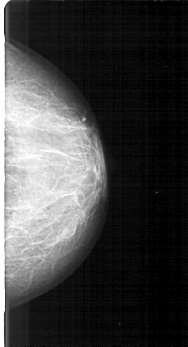

D_4127_1.RIGHT_MLO

RIGHT_MLO LINES 5296 PIXELS_PER_LINE 2881 BITS_PER_PIXEL 12 RESOLUTION 43.5 OVERLAY

FILE: D_4127_1.RIGHT_MLO.OVERLAY

LESION_TYPE CALCIFICATION TYPE AMORPHOUS DISTRIBUTION CLUSTERED

ASSESSMENT 3

SUBTLETY 2

PATHOLOGY MALIGNANT